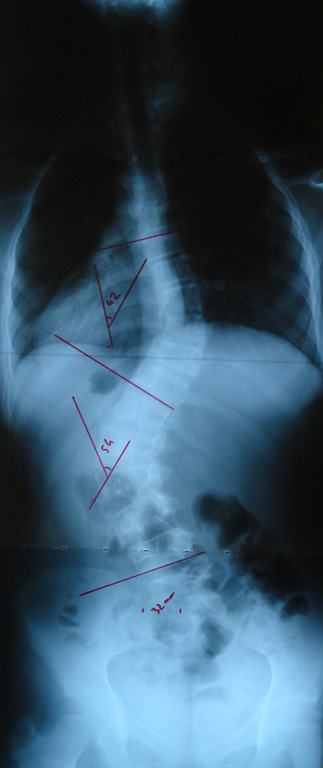

Grafilerle Skolyoz